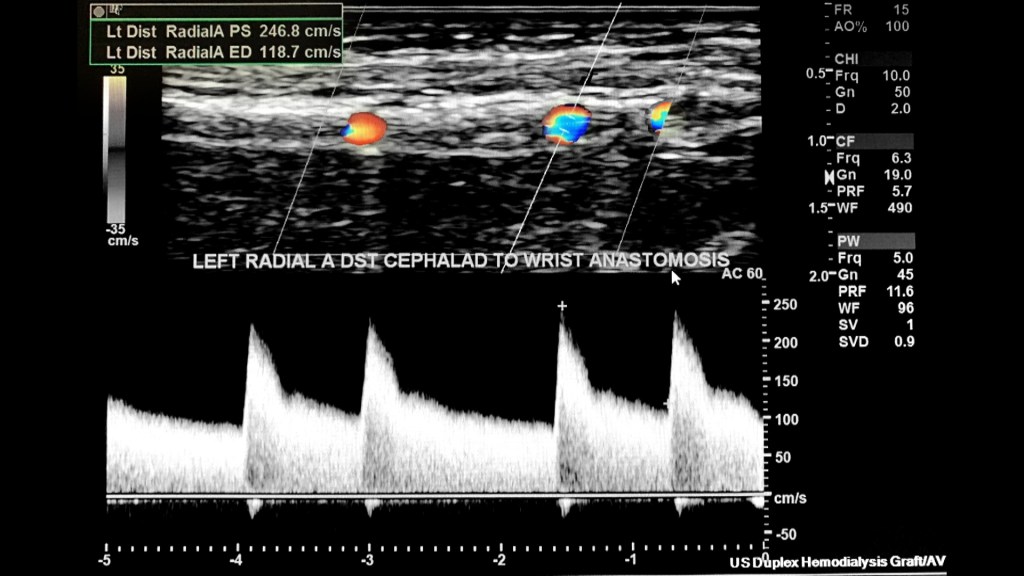

The normal spectral arterial tracing (inflow) proximal to the AVF will be a lower resistant high flow waveform followed by a higher resistance waveform distal to the anastomosis (make sure to evaluate for steal syndrome). The spectral analysis in the radial artery proximal to anastomosis has a high PSV/EDV at 247 cm/s and EDV at 119 cm/s.

I sampled the arterial anastomosis side a few times with the highest PSV/EDV as 673/354 cm/s.